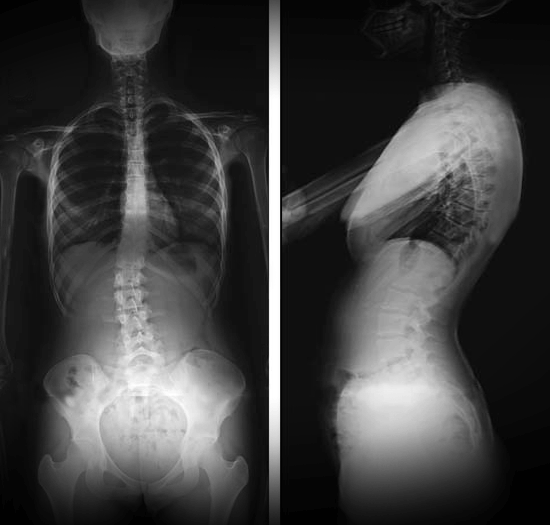

Radiografías de la columna vertebral

- Evalúan las causas de dolor vertebral, fracturas, tumores, alineación, alteraciones estructurales y enfermedades degenerativas.